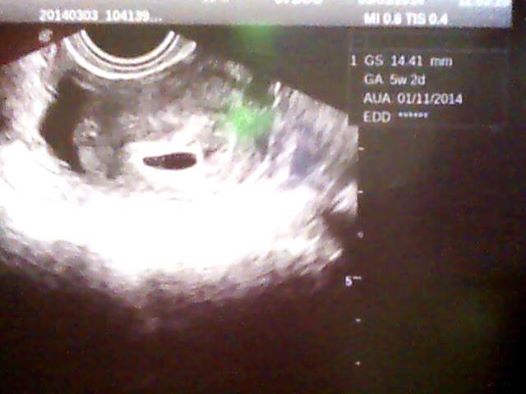

,tak jsem šla za chvíli na wc znova a čárka tam byla,to bylo ve čtvrtek ráno.V sobotu jsem si udělala další test a čárka byla vidět zase o něco lépe,takže jsme letěli v pondělí na gyndu,tam doktorka najela a říká no těhotenství tam je,ale úplně na začátku to byl tak 4 týden a říká za týden na kontrolu,o týden později to jsem byla 5+3 byl už vidět větší gestační váček i se žloutkovým,ale plod ještě vidět nebyl.A ted v pondělí to jsem byla 6+3 už byl vidět jak gestační váček,tak i žloutkový váček a plod se srdíčkem....dám sem všechny tři ultrazvuky at může porovnat jak to rychle roste

a tak ta první to je 4+3 ta druhá vedle ní to je 6+3 a ta spodní v druhém příspěvku je 5+3